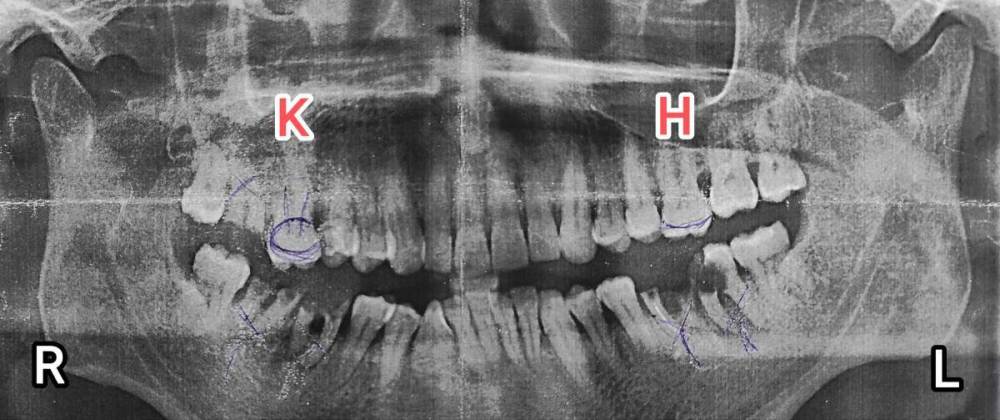

Примерно 3 года назад зубы 17,36,37,46,47 - из них повыпадали пломбы, последние 2 года из-за сложившихся обстоятельств не было возможности сделать зубы, пломбы туда ставил уже 10 лет, поэтому кромки зубов были тонкие и 1.5 года назад все по обламывались, остались только корни. Сейчас зубы в таком состоянии (смотрите панорамный снимок)

Скажите пожалуйста если сейчас вырвать 17,36,37,46,47 будет ли кость катастрофический размываться исчезать (* интересует состояние кости для последующей имплантации , через 2-3года) или кость 17,36,37,46,47 останется такой как есть???

1 ПАНОРАМА.jpg